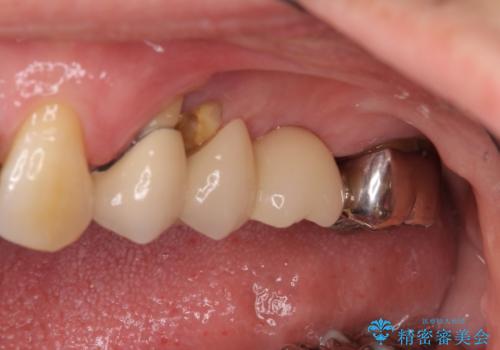

- 上の奥歯に装着されているブリッジが痛むとのことで来院された患者様です。

診察した結果、ブリッジの土台となっている歯が割れていたため、抜歯が必要となりました。

欠損している歯数が多いため、ブリッジによる補綴治療は困難と判断し、インプラントによる補綴治療を行うこととしました。